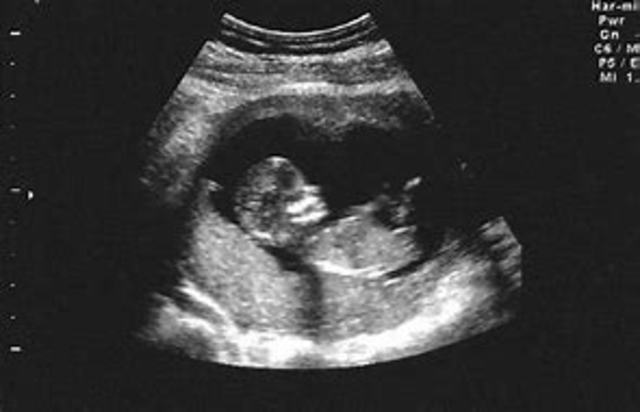

• The Ultrasound

The Ultrasound

The ultra sound was invented to see what was wrong in the stomach of a human being